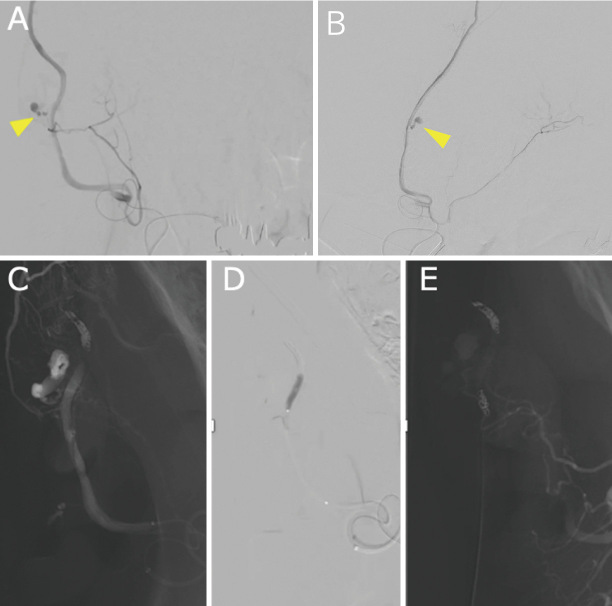

Patients with neurofibromatosis type 1 not only have characteristic skin findings but are also known to have vascular disorders due to vascular vulnerability. A 44-year-old man with previously undiagnosed neurofibromatosis type 1 was brought to the emergency room due to a sudden subcutaneous hematoma with no history of trauma. Angiography revealed extravasation from the parietal branch of the right superficial temporal artery, which was embolized with n-butyl-2-cyanoacrylate. However, the next day, the patient exhibited an increased subcutaneous hematoma, and new extravascular leakage was detected at the frontal branch of the superficial temporal artery, which was also embolized with n-butyl-2-cyanoacrylate. The patient had physical findings characteristic of neurofibromatosis type 1, such as café-au-lait spots, and was subsequently diagnosed with neurofibromatosis type 1. No obvious neurofibroma or any other subcutaneous lesion associated with neurofibromatosis type 1 was identified in the affected area. Massive idiopathic arterial bleeding in the scalp, although infrequent, can be fatal. Neurofibromatosis type 1 should be considered when a subcutaneous scalp hematoma is observed without a history of trauma, even if the facial skin structure appears normal. Neurofibromatosis type 1 is also known to have multiple sources of hemorrhage. Thus, it is important to repeatedly evaluate vascular structures via cerebral angiography, contrast-enhanced computed tomography, and magnetic resonance imaging, if necessary.